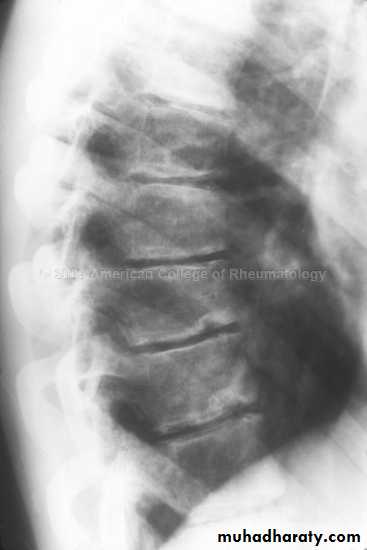

In the Spine :

* Lower cervical and low lumbar spine are most comonly affected.* Osteophytes may encroach on neural foramina (best seen on oblique views).

*Vacuum phenomenon: gas (N2),is pathognomonic of the degenerative process.

* OA of the spine occurs in the apophyseal joints .

* Degenerative spondylolisthesis (pseudospondylolithesis)

Lumbar spondylosis. There is distal narrowing and a vacuum

phenomenon is present in the degenerative discs. Marginal osteophytes arepresent. Inferiorly the facet joints show features of degeneration and, with the increase in lordosis, the spinous processes are in contact